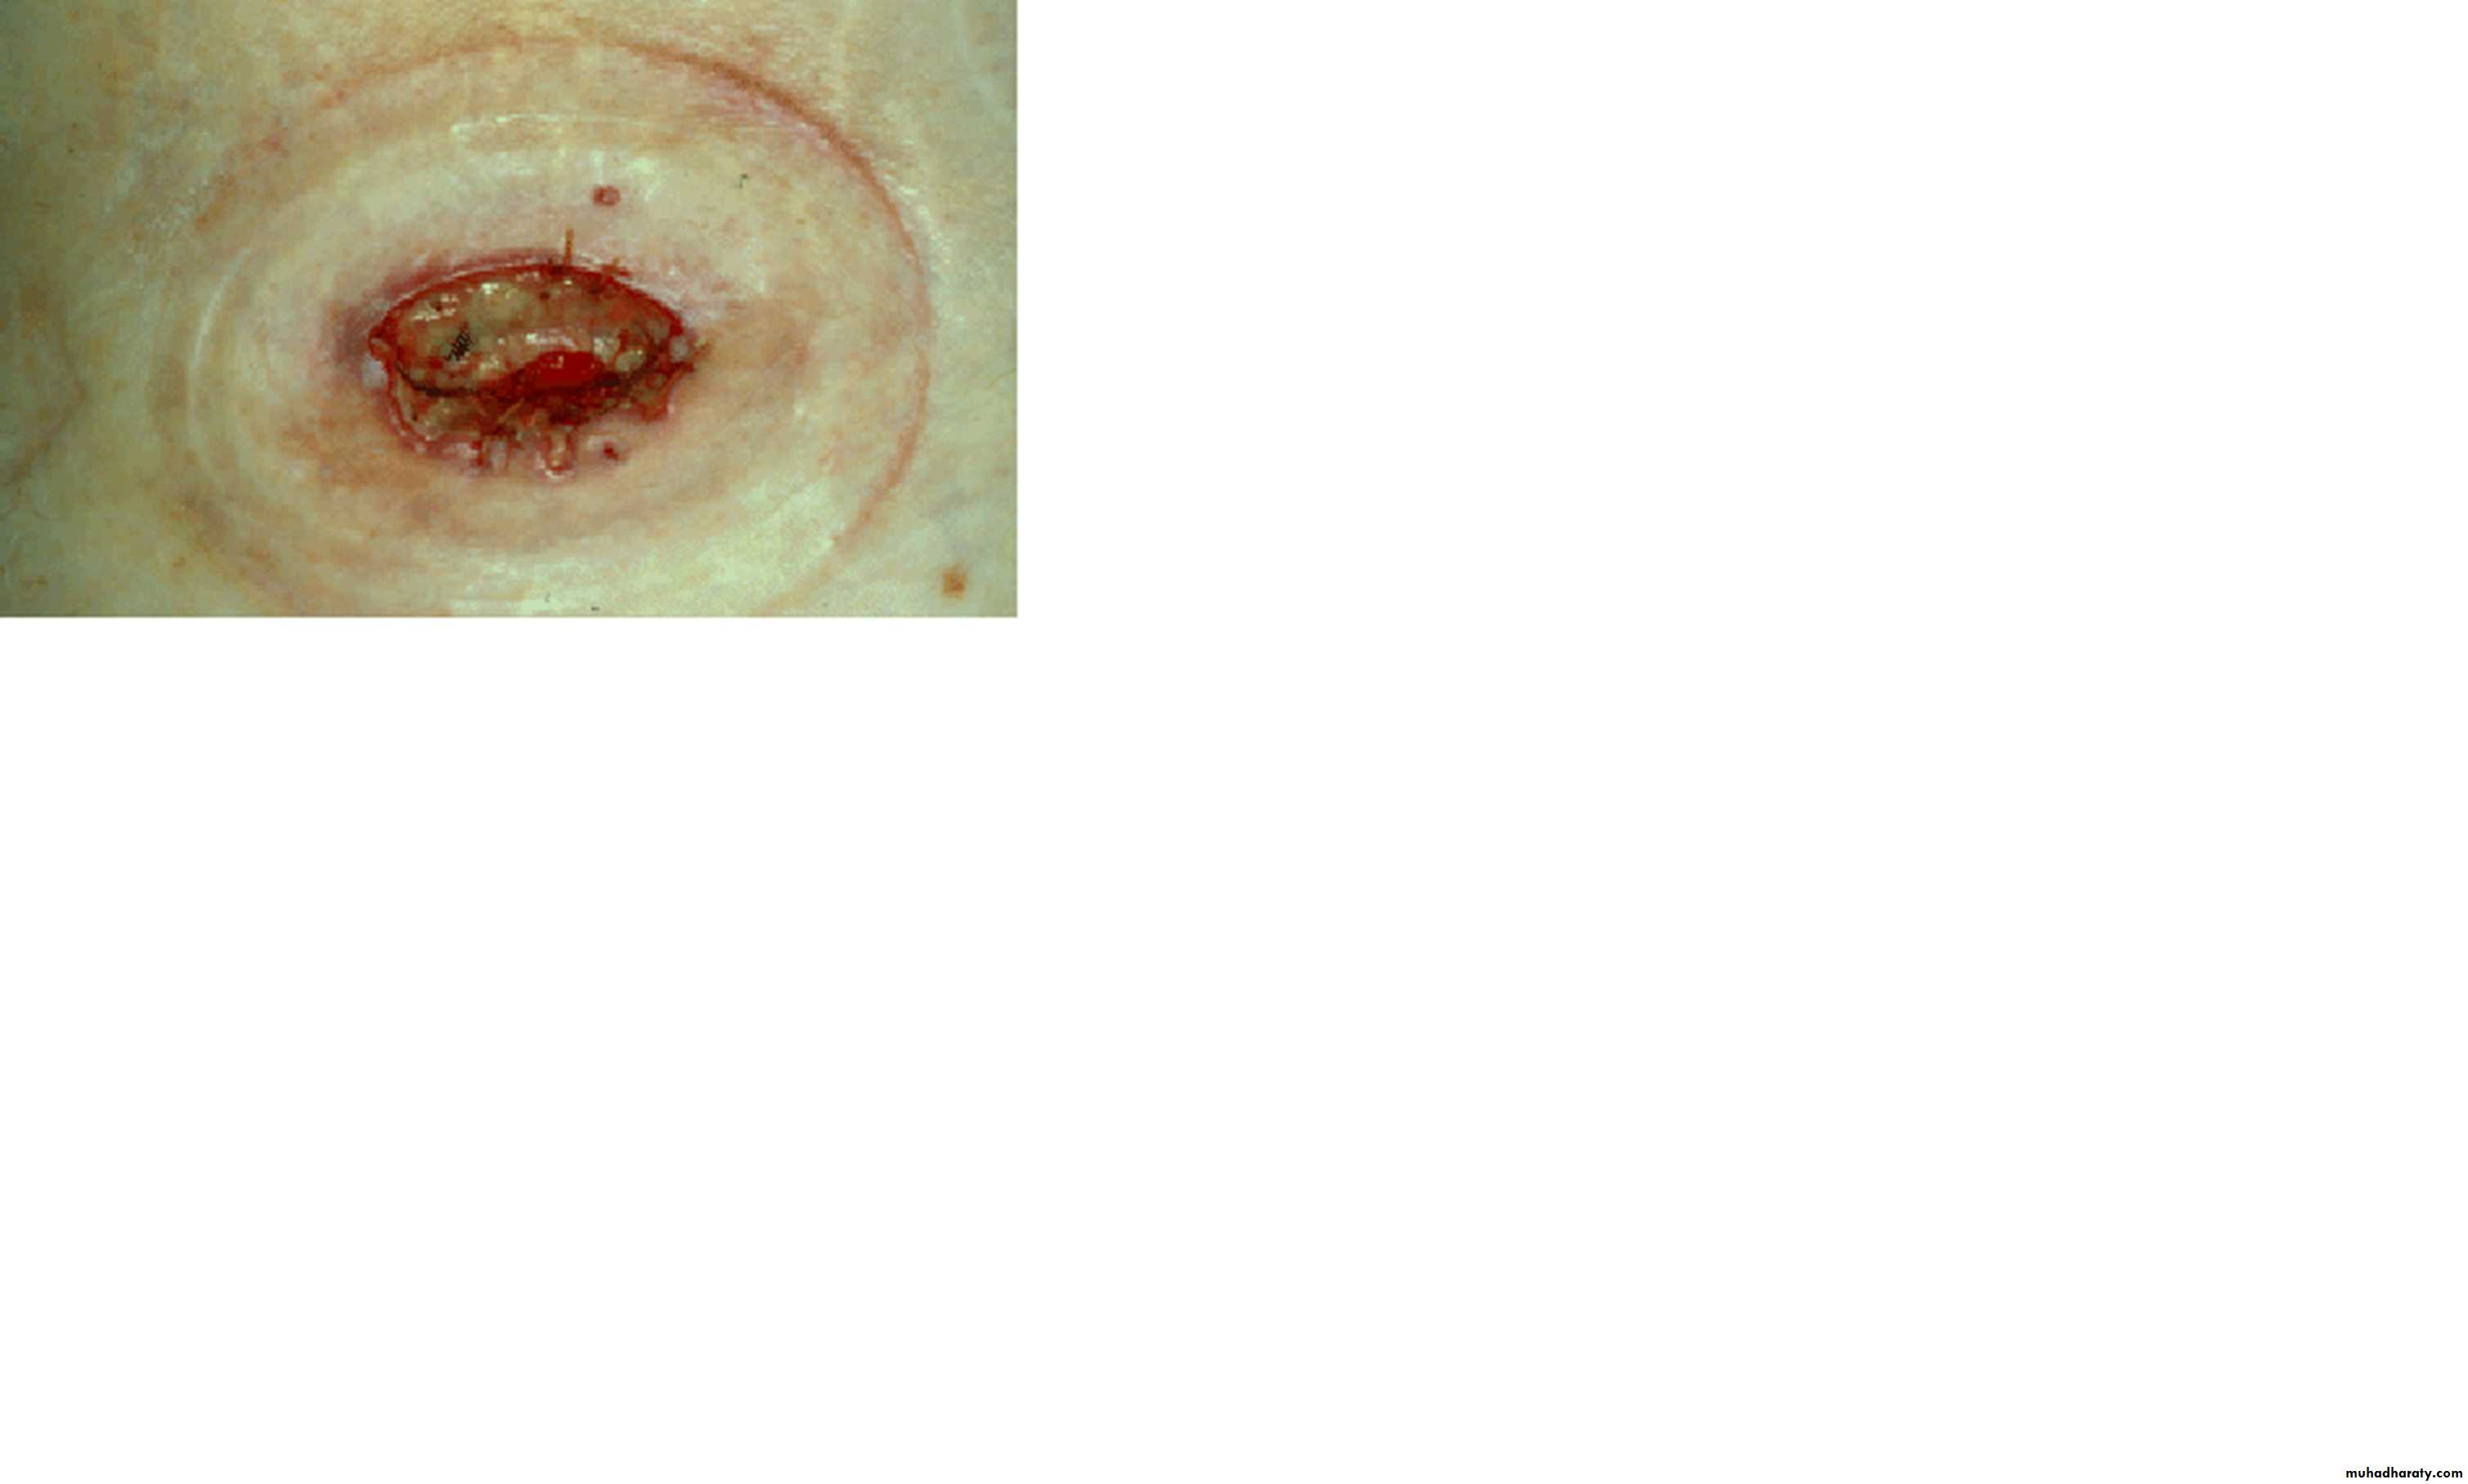

Slide 161- What type of gangrene is this?2- Give 2 predisposing factors